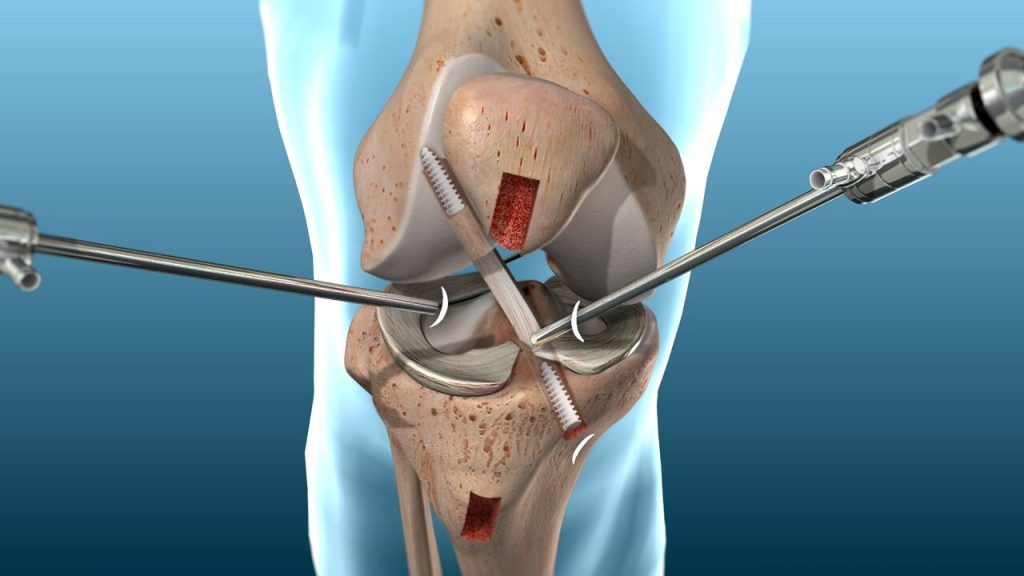

Ligament Repair

Ligament repair is a surgical or non-surgical procedure aimed at restoring the function and stability of a torn or damaged ligament, which is a strong band of tissue connecting bones...